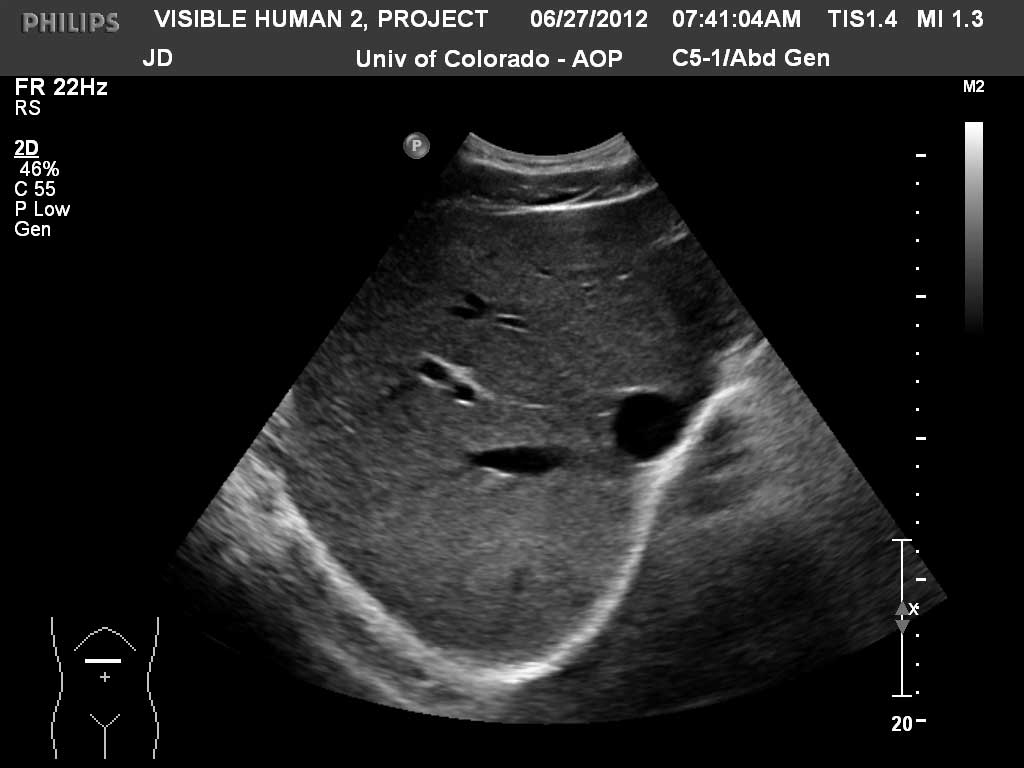

Transverse Liver

Index

Inferior Vena Cava

Liver

Right Hepatic Vein

Right Portal Vein